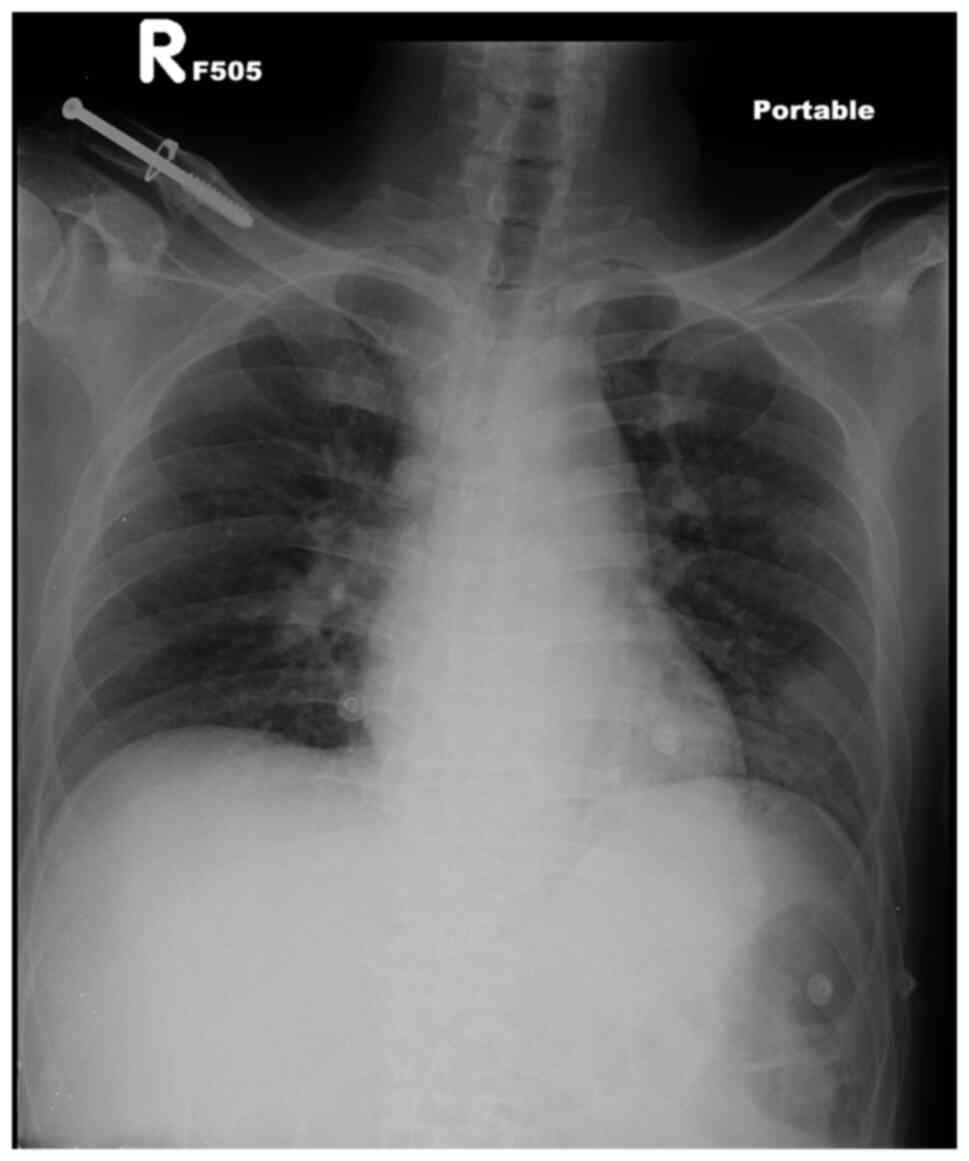

A 40-year-old male with a history of alcohol and drug addiction visited doctors in the Emergency Department of MacKay Memorial Hospital, Tamshui branch, Taiwan due to a persistently high fever for 1 day. He reported the abuse of drugs via intravenous injection and excessive alcohol consumption over the past 2 days. Upon arrival to the department, a physical examination revealed the following: A body temperature of 39.4˚C, a respiratory rate of 18/min, a heart rate of 115 beats/min and a blood pressure of 131/75 mm Hg. In addition, generalized skin gangrene was observed over the trunk (Fig. 1), buttocks and four limbs (Fig. 2A and B). Laboratory tests revealed a white blood cell count of 6,100/µl, a neutrophil count of 77%; thrombocytopenia (platelets, 67,000/µl) and elevated C-reactive protein (30.4 mg/dl), creatine kinase (>20,000 IU/l) and D-Dimer (>10,000 ng/ml) levels. A chest computed tomography scan was arranged to exclude septic emboli, which revealed multifocal ground-glass opacities in both lungs and subcutaneous soft tissue and muscle swelling over the back and buttocks (Fig. 3). An abdominal and cardiac sonography was performed for the exclusion of other origins of infection. There was no vegetation of the heart chamber or other significant findings. The urinary drug screen was positive for ketamine and benzodiazepine. A chest X-ray revealed a pneumonia patch over the left lower lung field (Fig. 4).

Figure 4

Chest X ray illustrating ground glass opacity in the left lung field.